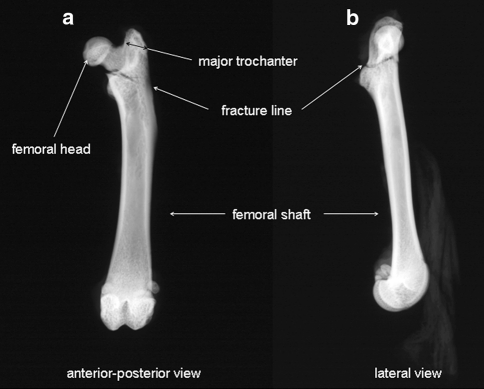

Radiographs in the anterior–posterior and lateral views were taken of all femurs tested in the study. A special film (SR type 45; Kodak, Rochester, NY) and a Faxitron fine-focus cabinet X-ray system (model 43855A; Faxitron X-ray System, Wheeling, IL) with 40 kV were used (Fig. 2).

Radiographs of the left femur of a Sprague–Dawley rat after the breaking test. Our breaking machine is able to produce reverse trochanteric fractures of the femurs (type A3 according to AO classification). a Anterior–posterior view. b Lateral view

Fracture Classification

We produced reverse trochanteric fractures of the femurs (type A3 according to the AO classification). All of these fractures showed great similarity in the localization and type of fractures. We observed in few cases a tilt of the femurs during the biomechanical test due to an inaccurate breaking curve. These cases were not taken into consideration. Here, we present data only from femoral trochanteric fractures as previously described [7] (Fig. 2).